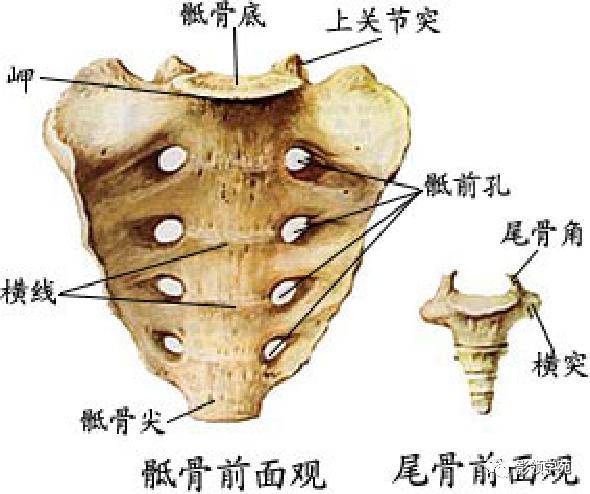

骨骼系统

骨骼系统